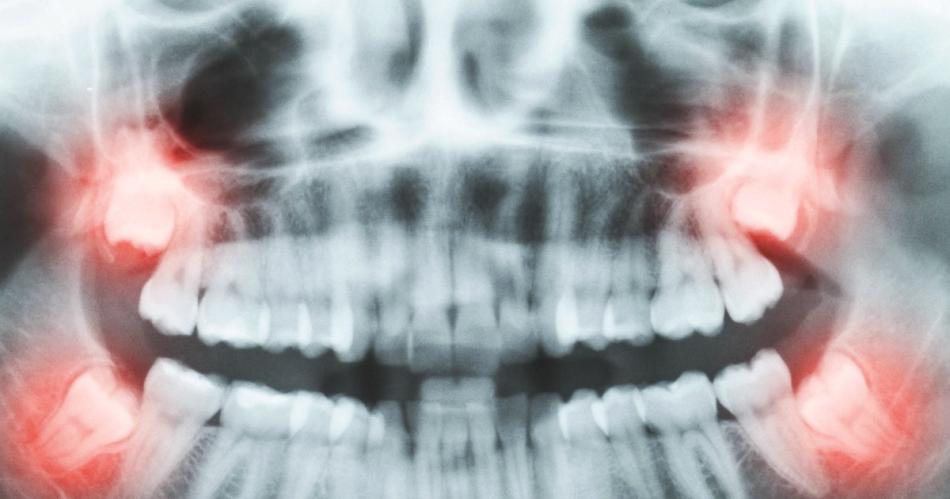

Las cordales son los terceros molares superiores e inferiores que están al fondo de la boca y que salen entre los 17 y los 21 años, en algunos casos pueden salir después. Estas muelas casi nunca tienen el espacio suficiente para salir o desarrollarse en normalidad como las demás, se presentan en 2 arriba y 2 abajo. Cuando las muelas del juicio están retenidas, producen síntomas como la inflamación y el dolor, estas son necesarias de radiografías porque vienen mal posicionadas en la mayoría de los casos. Los médicos recomiendan que sean extraídas así logren emerger sin ningún problema, para así evitar futuras complicaciones y que queden expuestas a las caries dentales, ya que por su posición en la parte más atrás de la boca, es más difícil su limpieza.

La Dra Gülay de la clínica dental Dentakay, de Turquía, expresa que el cirujano maxilofacial siempre debe examinar si es necesario la extracción de las muelas que están totalmente cerradas o parcialmente hacia afuera, y esto solo se logra por medio de radiografías para observar si vienen mal posicionadas. Recuerda que debes siempre visitar a un odontólogo de confianza que te realice los exámenes correspondientes antes de cualquier tratamiento dental

La opción más segura para las muelas del juicio es extraerlas, el odontólogo evaluará la situación de estás por medio de la radiografía panorámica, la intervención la realiza un cirujano por medio de anestesia local, en algunas ocasiones cuando la muela no se puede extraer fácil, se realiza una incisión de la encía para poder llegar a la muela, partirla en varios pedazos e ir sacándola poco a poco. Luego terminada la intervención se realiza una pequeña sutura que se retira en la consulta en unos 7 a 10 días luego del proceso.